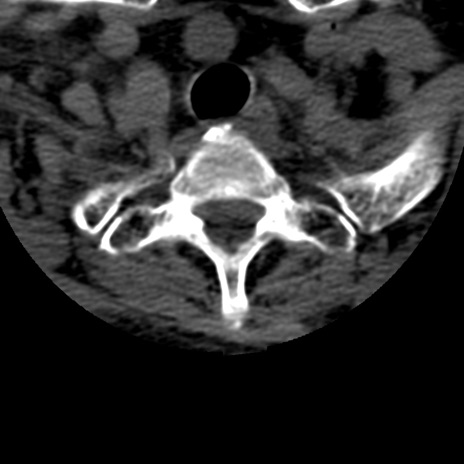

症例50 頚椎CT(横断像)

頚椎CT